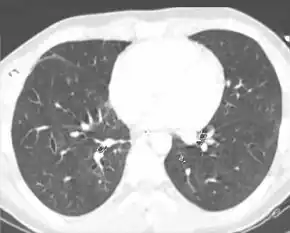

A chest CT scan revealing a pulmonary contusions due to being hit by a baseball bat

Computed tomography (CT scanning) is a more sensitive test for pulmonary contusion,[3][32] and it can identify abdominal, chest, or other injuries that accompany the contusion.[37] In one study, chest X-ray detected pulmonary contusions in 16.3% of people with serious blunt trauma, while CT detected them in 31.2% of the same people.[45] Unlike X-ray, CT scanning can detect the contusion almost immediately after the injury.[42] However, in both X-ray and CT a contusion may become more visible over the first 24–48 hours after trauma as bleeding and edema into lung tissues progress.[46] CT scanning also helps determine the size of a contusion, which is useful in determining whether a patient needs mechanical ventilation; a larger volume of contused lung on CT scan is associated with an increased likelihood that ventilation will be needed.[42] CT scans also help differentiate between contusion and pulmonary hematoma, which may be difficult to tell apart otherwise.[47] However, pulmonary contusions that are visible on CT but not chest X-ray are usually not severe enough to affect outcome or treatment.[36]